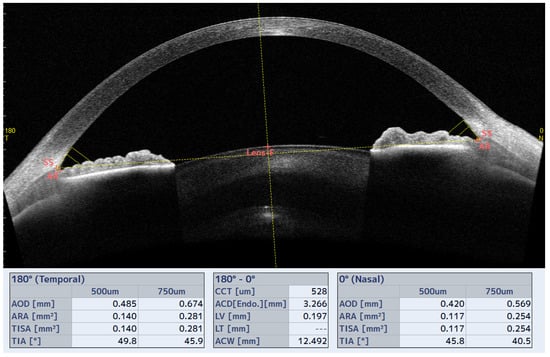

2.3. Measurement of Iridocorneal Angle (ICA) and Schlemm Channel (SC) Parameters